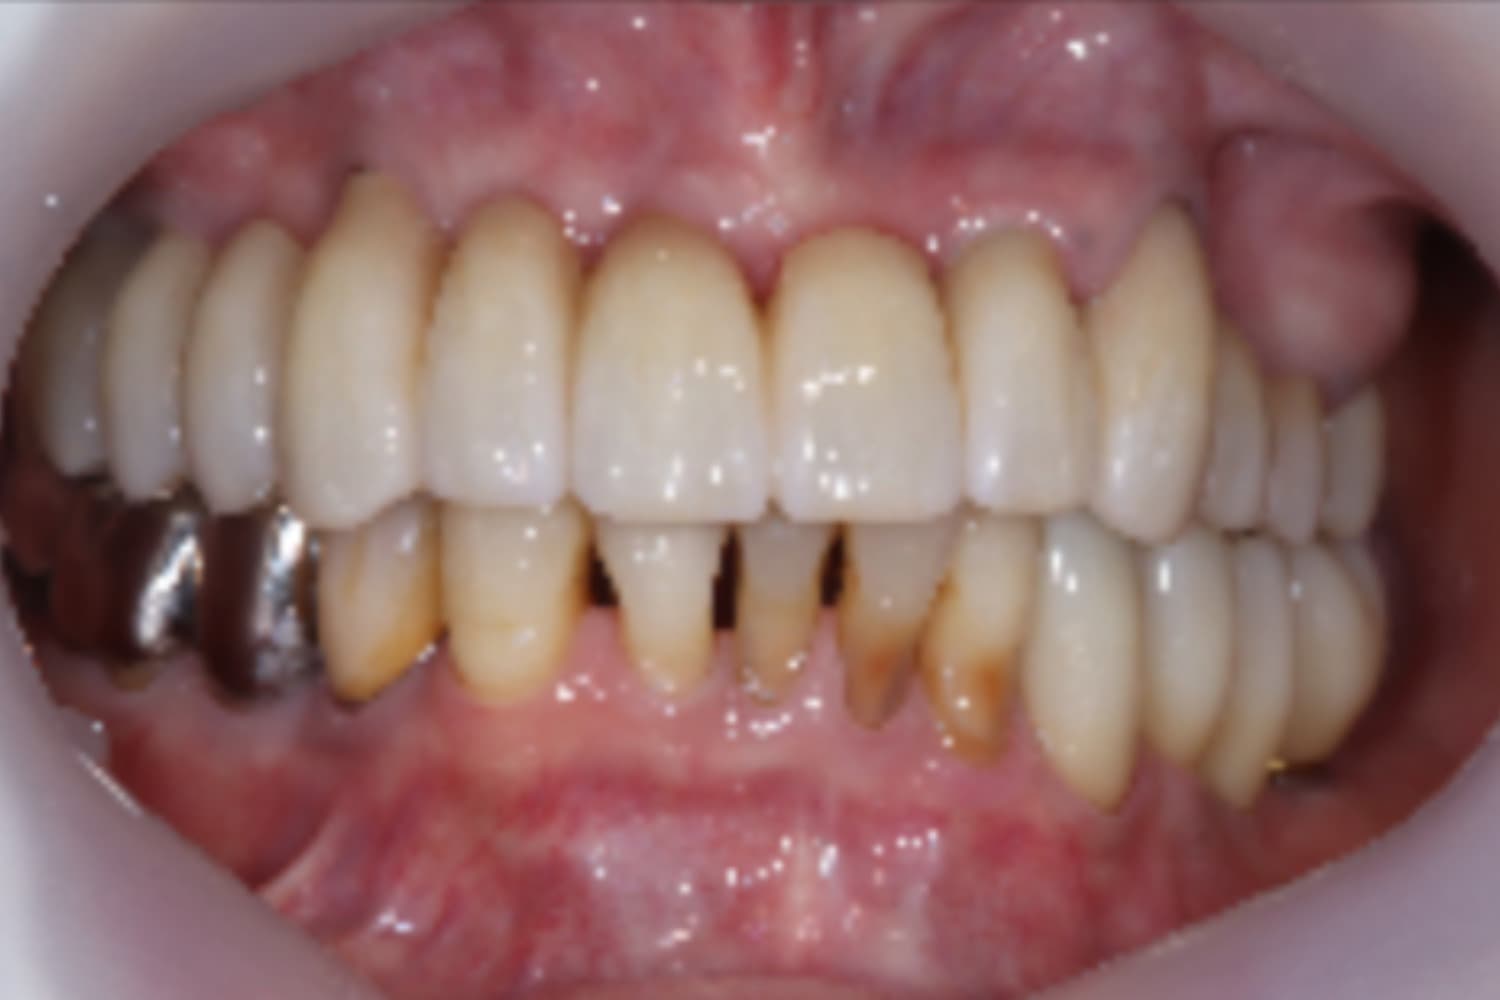

前歯と右上顎のインプラント治療

Before

After

左上の歯牙は何とか保存し、前歯と右上にインプラント治療を行なった。

主訴

前歯がぐらぐらする

治療期間

18カ月

治療回数

23回

費用

3,300,000円

副作用・リスク

・前歯にインプラントと同時に仮歯を装着したため、インプラントの骨結合不良リスクが高くなりました。 ・上顎洞底挙上術に伴い、上顎洞炎の発症リスクがあります。